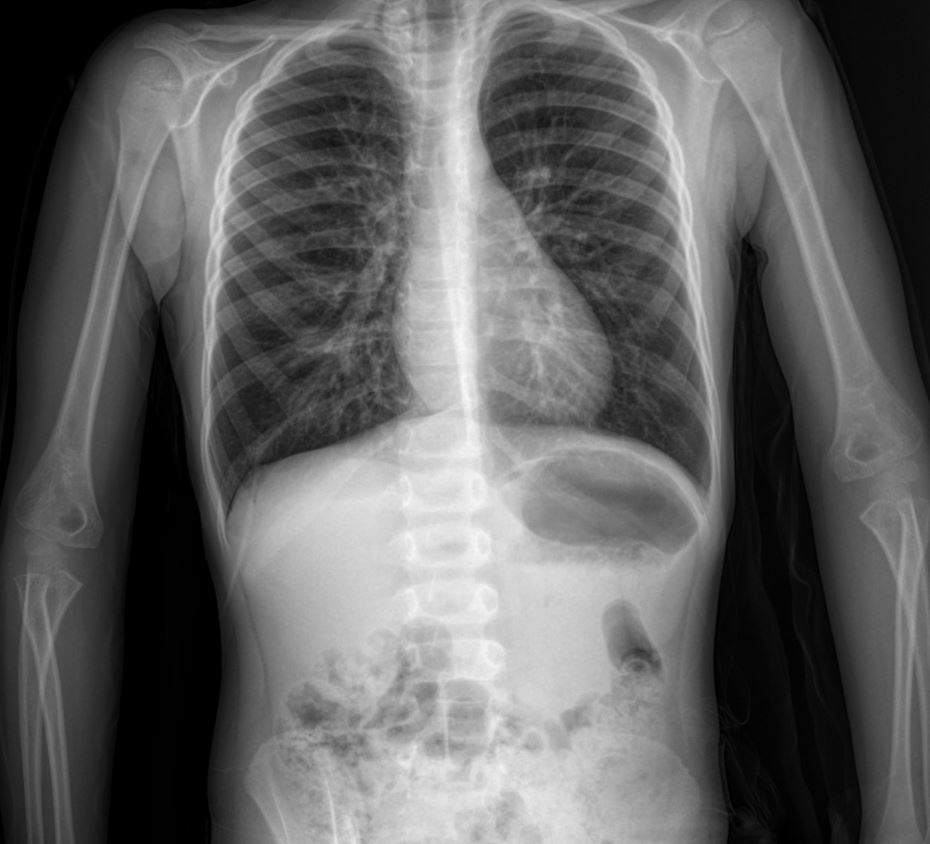

Chest X-ray Findings

The provided chest X-ray image (anterior-posterior view)

demonstrates several key features often seen in pediatric asthma exacerbations:

- Hyperinflation: While subtle, there are signs suggestive of hyperinflation, characterized by flattened diaphragms and increased retrosternal air space. This is due to air trapping in the lungs, a hallmark of bronchoconstriction and airway obstruction in asthma.

- Peribronchial Cuffing: There is evidence of peribronchial cuffing, appearing as increased density around the bronchi. This indicates bronchial wall thickening due to edema and inflammation, contributing to airway narrowing.

- Increased Bronchovascular Markings: The lung fields show increased prominence of bronchovascular markings, reflecting the inflammatory process and potentially some atelectasis or mucous plugging in smaller airways.

- No Focal Consolidation or Pneumothorax: Importantly, there is no evidence of focal consolidation, which would suggest pneumonia, or pneumothorax, a potentially life-threatening complication. This helps to narrow down the differential diagnosis in a child presenting with acute respiratory distress.

- Normal Cardiac Silhouette: The cardiac silhouette appears normal in size and contour, indicating no cardiomegaly or other significant cardiac pathology contributing to the respiratory symptoms.

This case exemplifies a typical presentation of an acute asthma exacerbation in a young child with a significant history of recurrent respiratory issues, despite lacking a formal asthma diagnosis prior to this admission. The presence of bilateral wheezing, prolonged expiration, and desaturation are classic signs. The chest X-ray findings, particularly hyperinflation and peribronchial cuffing, are consistent with an asthma flare-up, while ruling out other acute lung pathologies. The comprehensive treatment regimen, including bronchodilators, corticosteroids, magnesium sulfate, and antibiotics (likely for potential co-existing infection or as a broad-spectrum approach given the severity), reflects standard management protocols for severe asthma exacerbations. The family history of asthma and personal history of allergic rhinitis further support the underlying atopic predisposition common in asthmatic patients. Long-term management will likely involve formal asthma diagnosis, trigger avoidance strategies, and a tailored maintenance therapy plan.